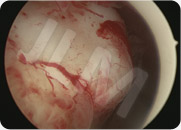

An operative hysteroscopy is inserted into the uterine cavity and it is equipped with a resectoscope (a cutting loop). The loop cuts the fibroma(s) into thin slices (as a plane might slice a potato into thin strips).

The slices of fibroma (myoma) are extracted from the uterus and then sent for analysis (to verify their constitution).